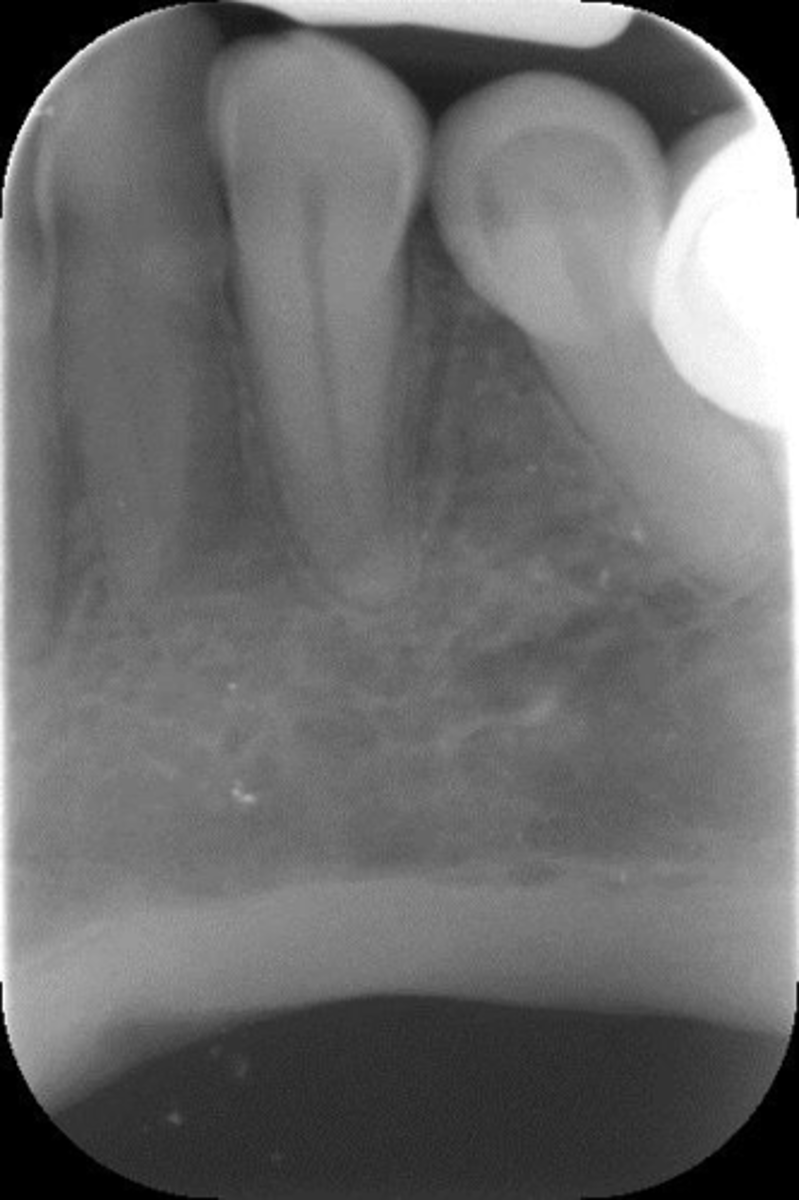

Elongated, vertical angulation, film holder (metal bar)

What is this error?